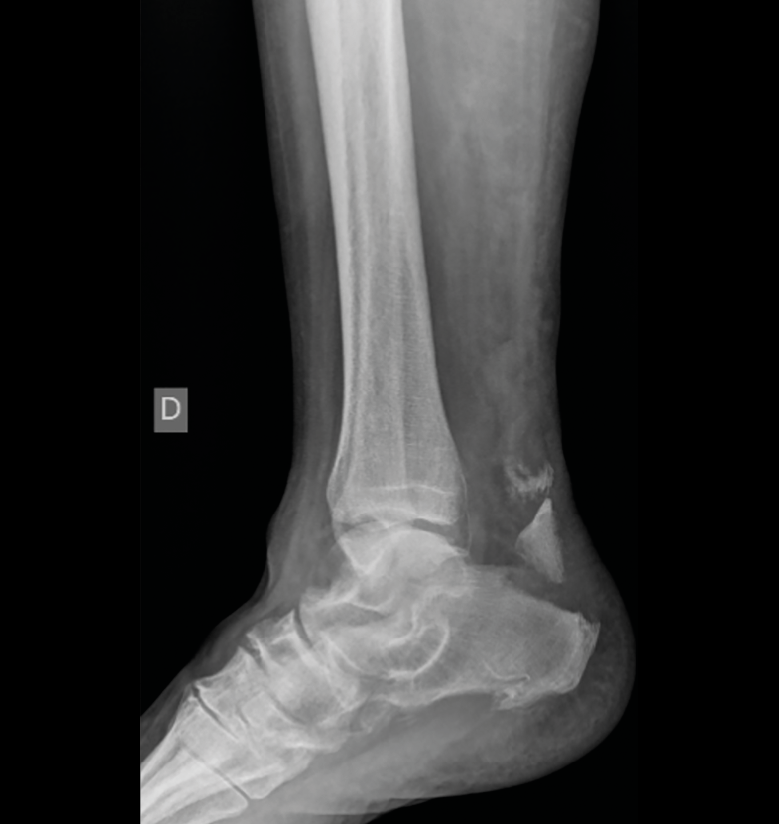

Figura 1. Radiografía de perfil que muestra una fractura avulsión de la tuberosidad posterior del calcáneo desplazada.

Presentamos el caso de una mujer de 69 años de edad que, en enero de 2019, sufre una fractura por avulsión de la tuberosidad posterior del calcáneo derecho (Figura 1) tras un mecanismo de flexión dorsal forzada del tobillo mientras sube unos escalones. Basándonos en la clasificación morfológica de Beavis (Figura 2), se trata de una fractura de tipo II. Según las mediciones realizadas sobre las radiografías simples y la tomografía computarizada, el desplazamiento resultó de 30 mm.